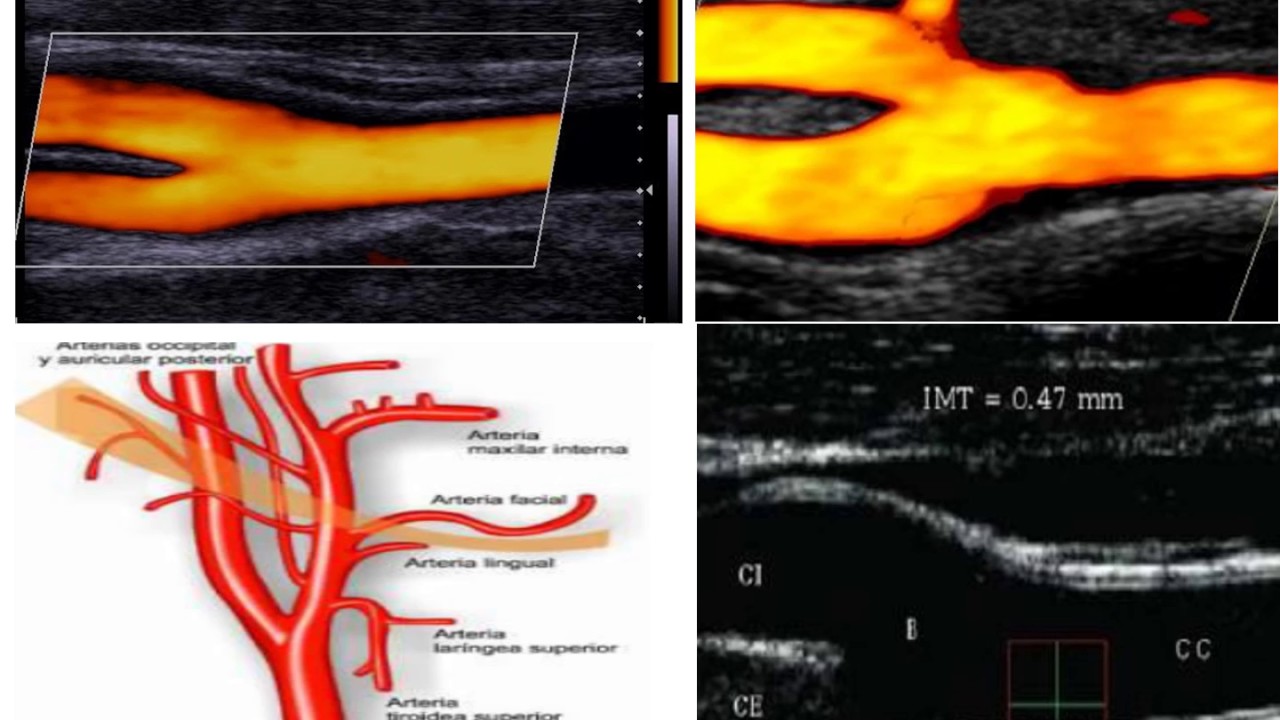

Eco Doppler De Troncos Supraaórticos, , , , , , , 0, Eco Doppler Troncos Supraaórticos - Centro Médico ENOVA, centromedicoenova.com, 585 x 585, jpeg, WebEl eco-doppler de los troncos supraaórticos, también conocidos como vasos carotídeos o epiaórticos, es un examen diagnóstico no invasivo dedicado a las. Web¿Qué es un eco doppler de troncos supraaorticos? Se trata de un tipo de estudio especial en donde se puede ver las arterias que irrigan el cerebro. Se podrán ver tanto las., 20, eco-doppler-de-troncos-supraaorticos, Novedades y Muebles WebEl eco-doppler de los troncos supraaórticos, también conocidos como vasos carotídeos o epiaórticos, es un examen diagnóstico no invasivo dedicado a las. Web¿Qué es un eco doppler de troncos supraaorticos? Se trata de un tipo de estudio especial en donde se puede ver las arterias que irrigan el cerebro. Se podrán ver tanto las.

WebEco Doppler-Troncos Supraaórticos. control 2 mayo, 2019. Lorem ipsum dolor sit amet, consectetur adipiscing elit. Donec vel imperdiet leo. Etiam risus ex, lacinia eget. WebEl Doppler transcraneal es un complemento del examen de los vasos supraaórticos que permite conocer el estado de la circulación en el cerebro y si se. WebLa eco-Doppler de troncos arteriales supra-aórticos, es una técnica de exploración diagnóstica en tiempo real, no invasiva y no utiliza radiaciones. Oclusiones. WebEl EcoColorDoppler de Troncos Supraórticos (TSA) es un examen no invasivo que permite la evaluación morfológica (permeabilidad y calibre) y. WebEco-doppler de TSA (troncos supra-aórticos) en Hospital Casa de Salud. En el Hospital Casa de la Salud de Valencia puedes hacerte un doppler que permite comprobar el. Web¿Qué es un Eco-Doppler Supraáortico? Es una prueba diagnóstica de imagen no invasiva mediante ultrasonidos, para estudiar las arterias que irrigan el cerebro (carótidas y. WebMe han realizado un doppler de troncos supraaórticos porque tengo mareos y me ha salido todo bien, esto quiere decir que no voy a sufrir un ictus y que me riega bien. WebEl estudio mediante ecografía Doppler permite visualizar en tiempo real lo vasos sanguíneos arteriales y venosos de la circulación a nivel cervical e intracraneal. Es una.

WebAutor y referencias. ¿Troncos supraaórticos eco-doppler en reposo? El ecodoppler del tronco supraaórtico (TSA) es una prueba que se utiliza para estudiar y controlar los. WebEcógrafo Doppler. DESCRIPCIÓN. La ecografía de troncos supra aórticos (TSA) permite el estudio de las arterias que irrigan el cerebro (carótidas y vertebrales). CÓMO HE DE.